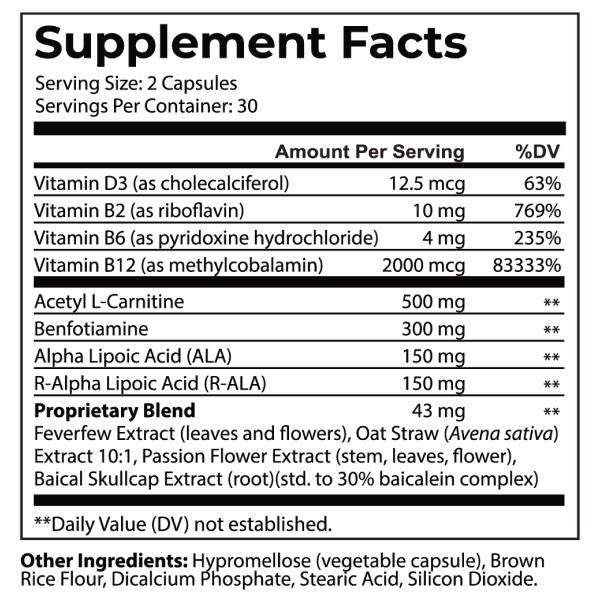

INGREDIENTS:

Vitamin D3

Vitamin D3:

Dramatically reduces nerve impairment symptoms in studies! Studies show a correlation between Vitamin D deficiency and nerve dysfunction symptoms. It’s also linked to blood vessel complications and the inability to sense cold temperatures. Vitamin D helps improve small nerve fiber function. This sunshine vitamin is essential for healthy nerve function and glucose control! ***

Vitamin B2

Vitamin B2:

Riboflavin can be a lifesaver to some nerve dysfunctions! Some symptoms, including weakness, hearing loss, sensory ataxia (sensation loss in hands and legs), eating, and respiratory difficulties, could be caused by a Riboflavin transporter deficiency. Riboflavin aids mitochondrial activities, free radical defense, and reduces excess pro-inflammatory molecules. Studies show supplementing with Riboflavin can alleviate these symptoms!****

Vitamin B6

Vitamin B6:

Vitamin B6 can alleviate deficiency-caused nerve dysfunction symptoms! These can include pins and needles, burning, shooting, and tingling discomfort in your arms, legs, hands, and feet. It can also result in difficulty walking, clumsiness, and balance problems. Pyridoxine protects against isoniazid-induced peripheral nerve dysfunction. A study of patients with nerve impairment given Vitamin B6 for 4 months resulted in over 66% showing significant improvement in discomfort and symptoms.*** Pyridoxine, a potent ally!

Vitamin B12

Vitamin B12:

Deficiency of B12 is linked to nerve impairment! Vitamin B12 promotes the regeneration of nerves by boosting protein synthesis. It’s essential for maintaining healthy nerves and protecting them from damage. B12 helps reform, build, and support the protective myelin sheath insulation of nerves. Damage to the myelin sheath leads to nerve discomfort and interruption in signaling. *** Helps rebuild and regenerate myelin insulation!

Acetyl-L-Carnitine (ALCAR)

Acetyl-L-Carnitine (ALCAR):

Alleviates symptoms! Studies demonstrate that ALCAR is effective in alleviating symptoms and discomfort, improves vibration perception, and nerve fiber regeneration.*

Benfotiamine

Benfotiamine:

Beneficial Benofotiamine! This form of Vitamin B1 (Thiamine) is 3.6 times better absorbed and multiplies metabolic activity levels by a factor of 120. Being fat-soluble improves its ability to penetrate nerves. Studies show it reduces advanced glycation end-products (AGEs) by 40%, inhibiting damage to blood vessels caused by impaired glucose metabolism. Studies show it increases signaling speed, reduces discomfort and HbA1c levels. It improves nerve scores significantly!***

R-alpha-lipoic acid (RALA)

R-alpha-lipoic acid (RALA):

RALA is a potent free radical scavenger that can delay or reduce nerve decay and its symptoms! Imbalanced blood glucose increases free radicals, which starve nerves of oxygen, causing impairment. RALA increases your body’s natural antioxidant glutathione activity, delaying and alleviating peripheral nerve symptoms caused by impaired blood sugar metabolism. RALA is the only form that functions as a co-factor for mitochondrial enzymes involved in energy production. Studies show it significantly reduces the intensity, burning, unpleasantness, and superficial discomfort.***

Feverfew Extract

Feverfew Extract:

Fabulous Feverfew regenerates nerve growth! Exciting recent studies show a compound called parthenolide accelerates nerve re-growth and improve its functional outcome. It helps reduce immunity markers of hyperactive immunity associated with neuropathy. Feverfew also helps reduce your discomfort!*

Oat straw extract

Oat straw extract:

Oat Straw Extract helps glycemic control! It can help reduce nerve dysfunction symptoms, including itchy or irritated skin, swelling, hyperactive immunity markers, and discomfort. It also improves peripheral blood flow to the hands and feet, supporting nutrient and oxygen delivery for regeneration.* And it soothes the nervous system and eases feelings of jitteriness!****

Passion flower herb extract

Passion flower herb extract:

Passionflower calms the overactive impaired nerves! This hypersensitive nervous system and discomfort often leads to feelings of nervousness and interrupts sleep. Passionflower increases the neurotransmitter GABA (Gamma-Aminobutyric Acid), which slows brain activity. Passionflower calms both emotional and physical nerves and helps you sleep! ***

Baical skullcap root extract

Baical skullcap root extract:

Alleviates nerve dysfunction symptoms! By increasing blood flow to the brain, Skullcap helps ease nervous feelings and calms your hyperactive nervous system. It also reduces discomfort associated with overactive immune responses. Studies show Skullcap’s flavonoid called Baicalin has important antioxidant properties and reduces discomfort in lab animals. Researchers conclude Skullcap protects against nerve damage!**

Alpha-Lipoic Acid

Alpha-Lipoic Acid:

ALA is a powerful, naturally occurring antioxidant co-factor produced in the mitochondria of every cell, which converts glucose into energy. Studies show mitochondrial energy stimulates nerves and regenerates nerve fibers, delaying decay and promoting the regeneration of impaired peripheral nerves. And ALA increases the body’s free radical scavenger, glutathione. It also activates vitamins C and E and CoQ10, key antioxidants that support nerve health. In addition, it influences AMPK, improving blood sugar metabolism, and chelates heavy metals that decay nerves and inhibit discomfort.**

What are the Effective Ingredients in NERVE REGEN FORMULA?

- Vitamin D3: Essential for nerve health and function. It could play a crucial role in nerve growth and maintenance while supporting overall neurological health.

- Riboflavin: A vital B-vitamin that helps protect nerve cells from oxidative stress and supports energy production in nerve tissue, promoting optimal nerve function.

- Vitamin B6: Critical for nerve development and function. It helps produce neurotransmitters and supports the maintenance of the nervous system's myelin sheath.

- Vitamin B12: A crucial nutrient for nerve health that helps rebuild and regenerate myelin insulation, essential for proper nerve signal transmission and reducing nerve-related discomfort.

- Acetyl-L-Carnitine HCl: Supports nerve function and helps maintain healthy nerve structure. It may help reduce nerve discomfort and improve nerve regeneration.

- Benfotiamine: A highly bioavailable form of vitamin B1 that could help protect nerves from damage and supports healthy nerve function.

- R-Alpha-Lipoic Acid: A powerful antioxidant that defends nerves against damaging factors. It could particularly be effective in supporting healthy nerve function.

- Feverfew Extract: Contains beneficial compounds, including parthenolide, which potentially accelerates nerve re-growth and supports overall nerve health.

- Baical Skullcap Root Extract: Traditional herb that could help calm overactive nerves and supports the body's natural comfort response.

- Oat Straw Extract: Known for its calming properties, it may help soothe nerve discomfort and supports overall nervous system health.

- Passion Flower Extract: Could promote relaxation and support the body's natural comfort response while calming overactive nerves.

We're committed to improving our formulas based on the latest research, which can affect serving size and cause slight variations in ingredients. Each ingredient is carefully selected and combined in precise amounts to support optimal nerve health and function. Please refer to the product label for the most accurate information about current formulations. Each premium ingredient in this doctor-approved formula is backed by scientific research and chosen specifically for its ability to support healthy nerve function through multiple pathways. Together, these ingredients work synergistically to provide comprehensive support for your nervous system health.